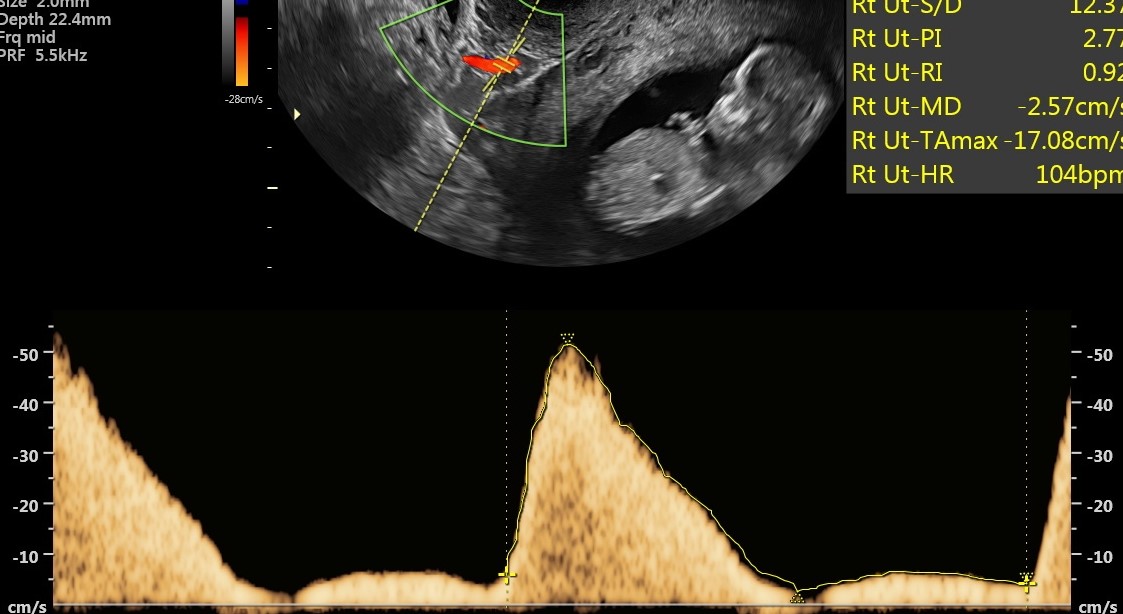

Prawidłowe przepływy w tętnicy macicznej w czasie ciąży, fot. USK-2

Kobietom objętym programem PRENATALPROJEKT wykonywane jest w 1. trymestrze badanie USG, mierzone jest ciśnienie oraz badane są trzy substancje, które pozwalają zdiagnozować funkcjonowanie łożyska i wykryć ww. patologie. Standardowe badania prenatalne obejmują badanie dwóch substancji i nie dają one wystarczająco miarodajnych i pewnych wyników co do prawidłowości funkcjonowania łożyska. W 2. trymestrze ciąży wykonywane jest już samo USG oraz badane ciśnienie. W przypadku wykrycia nieprawidłowości ciężarna zostaje objęta szczególną opieką i monitoringiem. W specjalnie utworzonej aplikacji, którą może pobrać na telefon i z której korzysta także jej ginekolog położnik, podaje mierzone kilka razy dziennie ciśnienie oraz wagę. Lekarz badań prenatalnych, biorący udział w programie decyduje o podjęciu leczenia. W przypadku niewydolności łożyska jest nim podanie odpowiedniej dawki aspiryny. Kobieta przyjmuje ją pod kontrolą lekarza do 36. tygodnia ciąży, który określany jest jako bezpieczny dla rozwoju dziecka, a rozwiązanie ciąży nie stanowi dla niego już takiego ryzyka.